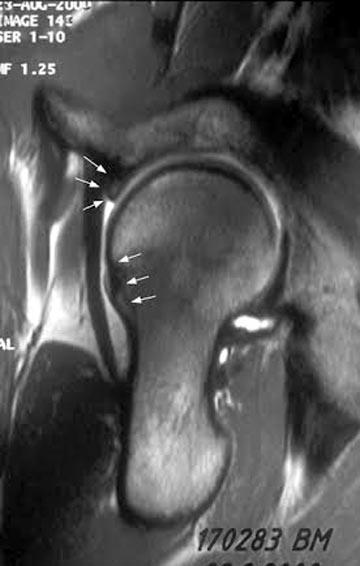

Обычно при внутрикостной кисте болевой симптом не проявляется, но капсула и лабральное кольцо из-за измененной анатомии могут быть причиной боли! Хроническая травма на шейке образует характерный бугор, меняется центр ротации, и во время нагрузки бугор выталкивает головку из вертлужной впадины. Это приводит к деламинации хряща, что не всегда определяется на рентген снимке. Поэтому следующим методом исследования становится МРТ с гадолинием, потому что другие исследования не покажут состояние лабриум и хряща!

Здесь представлены рентген, боковой, МРТ и клинические снимки деламинации хряща одного того же пациента.